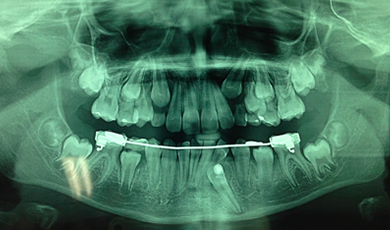

Canino inferior esquerdo incluso (dente 33)

As imagens abaixo retratam um caso clínico em que a paciente compareceu ao consultório para avaliação ortodôntica e por meio da imagem radiográfica (panorâmica) foi possível identificar que o canino inferior esquerdo (dente 33) encontrava-se incluso, sendo necessária a intervenção ortodôntica para o seu tracionamento.